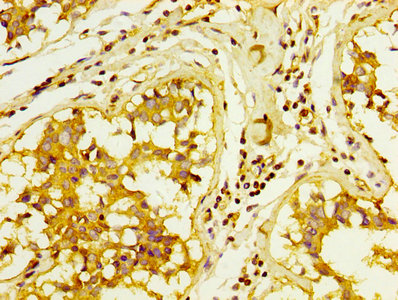

Immunohistochemistry analysis of human cervical cancer using CSB-PA10599A0Rb at dilution of 1:100